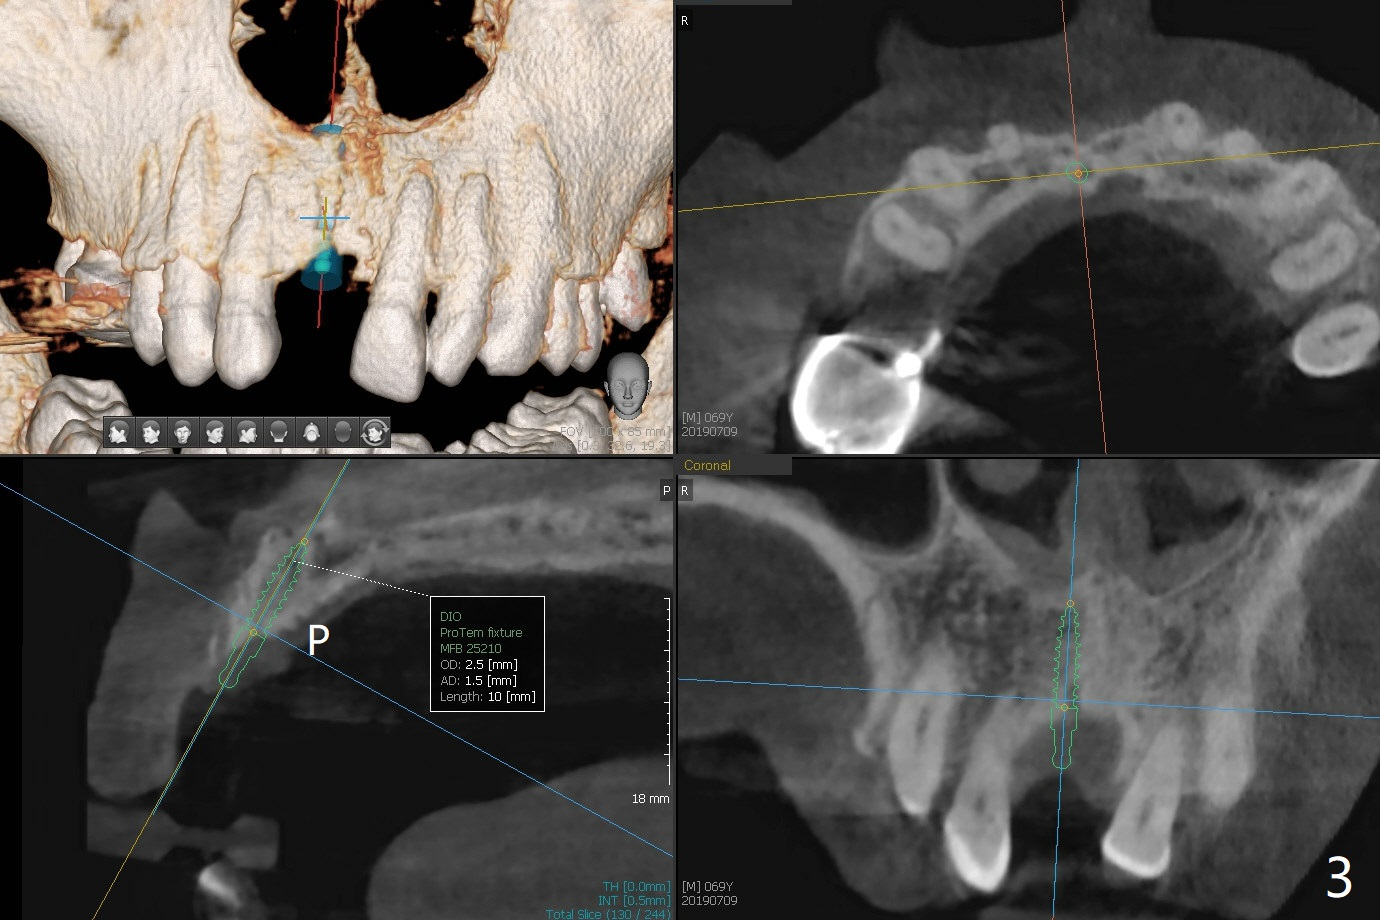

A 69-year-old man (ex-soldier) had the tooth #8 extracted for a flipper nearly 8 years earlier (Fig.1 (obliterated canal)). A denture tooth is added at #14 after extraction in NY a few years later (Fig.2). In spite of sufficient bone width at #8, a 2.5x10 mm mini implant will be chosen to reduce the chance of palatal thread exposure (Fig.3 P). A 5x8.5 mm implant will be placed at #14 to achieve enough stability and not cause sinus complication (Fig.4). Take preop photos to show the anterior deep overbite and overjet. In fact the patient canceled the surgery. Two years later, he returns with history of right TMJ dislocation, which may be related to reduced mastication efficiency and partial edentulism (Fig.5,6).